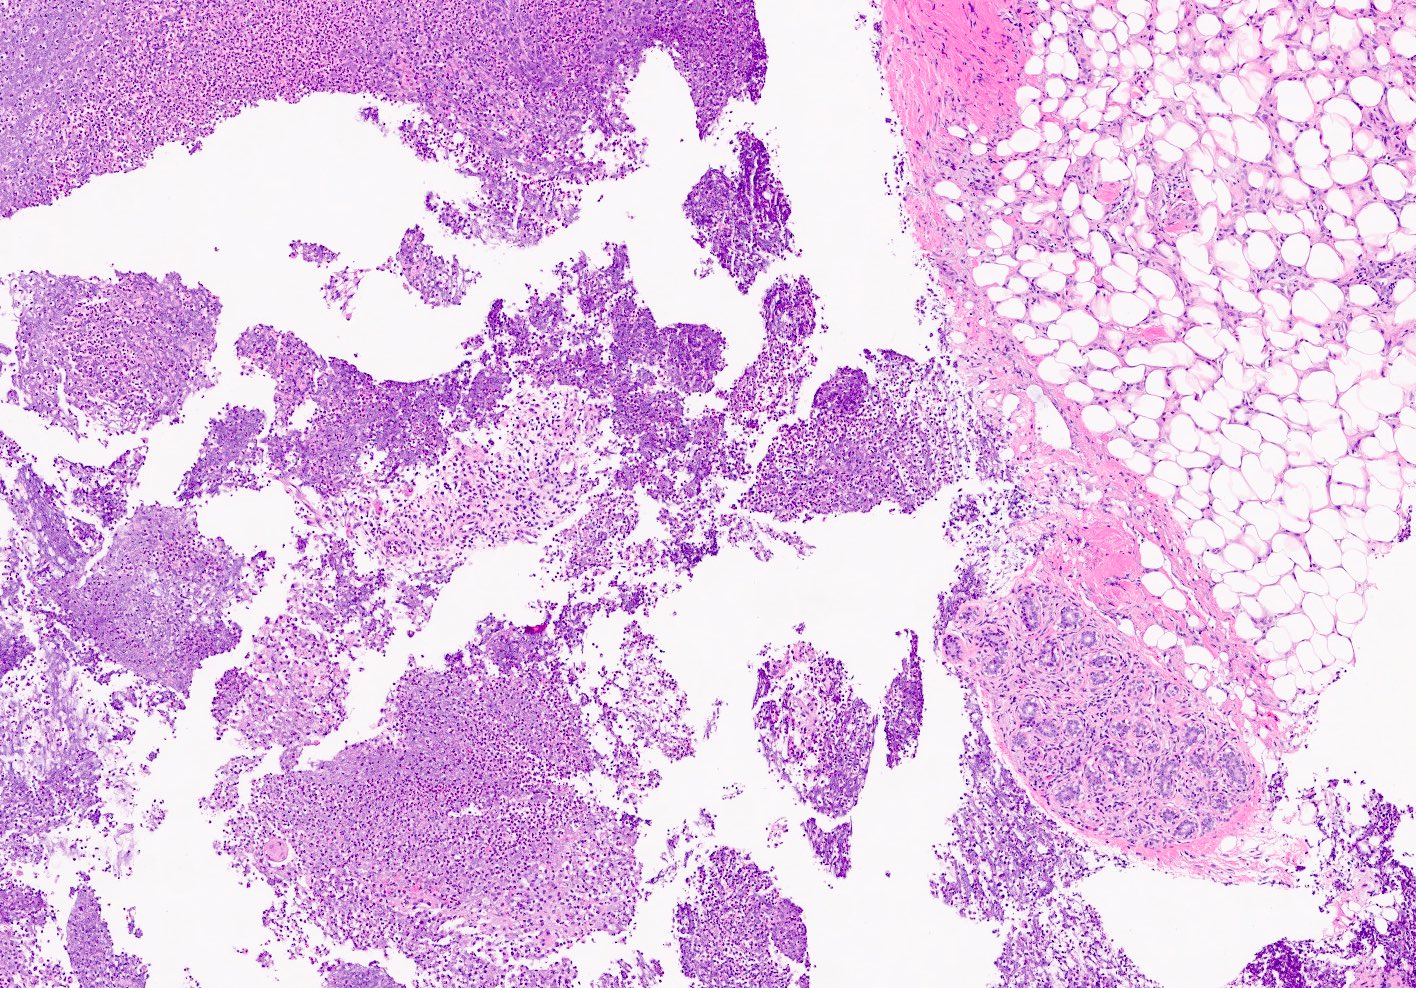

Microscopic (histologic) description

- Mixed dense inflammatory infiltrate, predominantly neutrophils, in breast tissue

- May obscure underlying normal breast tissue

- Tissue necrosis may be present

- Gram stain for microorganisms may reveal bacterial forms (gram positive cocci) associated with neutrophilic infiltrate

- Granulation tissue and chronic inflammation with resolution

- Lymphocytes, giant cells and granulomas are not typical (J Pathol Transl Med 2015;49:279)

Microscopic (histologic) images

Contributed by Kristen E. Muller, D.O.

Contributed by Ayesha Farooq, M.B.B.S. and Julie Jorns, M.D. (Case #515)